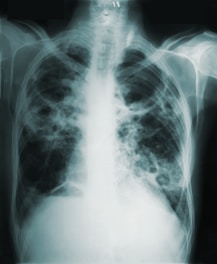

List of Disease